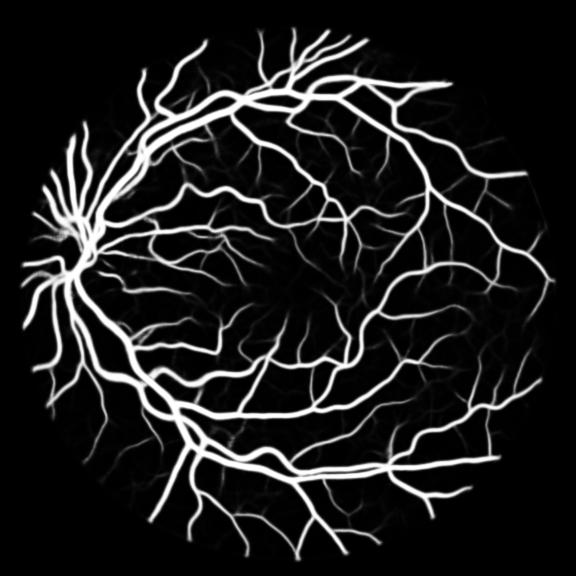

We perform retina blood vessel segmentation experiments on two different datasets, DRIVE[25] and CHASE_DB1[26]. DRIVE dataset consists of 40 retinal images in total, in which 20 samples are used for training and remaining 20 for testing. The size of each original image is 565584 pixels and all images are cropped and padded with zeros to 576576 to get a square dataset. We randomly select 531265 patches whose size is 4848 from 20 of the training images in DRIVE dataset and 10 of them are used for validation. Another dataset, CHASE_DB1, contains 28 color retina images with the size of 999960 pixels which are collected from both left and right eyes of 14 school children. 20 samples are randomly selected as training set and the remaining 8 samples are used for testing. Similar to DRIVE dataset, we crop all the samples into 960960 pixels and randomly select 412400 patches of 4848 pixels from the training set of which 10 are used for validation and the remaining for training.

All three datasets are processed by subtracting the mean and normalizing according to the standard deviation. We use Adam optimizer, set the initial learning rate to 0.001 which is reduced by ten times if the training set loss does not drop during 10 consecutive epochs. We augment data using rotation, crop, flip, shift, change in contrast, brightness and hue. We set batch size to 4 for Skin Dataset and 32 for DRIVE and CHASE_DB1 whose patch size is relatively smaller. For each model we train 50 epochs and the result is shown in Table 1. Models with MixModule have better performance than those not and the best performance in each metric all comes from MixModule-based models. We also show some outputs of the networks in Figure 4.